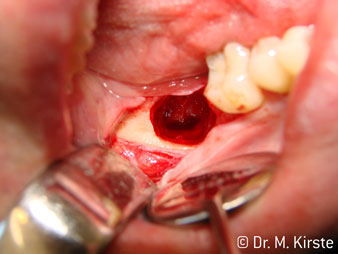

Угол 45° наконечника был выбран специально с учетом широкого круга преимуществ. Коллеги, которые работают в хирургии, и для которых этот наконечник был изначально создан, быстро оценят возможность эффективно работать в очень стесненном пространстве. В частности, при удалении зуба мудрости (рис. 2) не нужно сильно раздвигать мягкие ткани в области щеки (рис. 3). Конструкция головки наконечника в сочетании с небольшим поворотом головки во время препарирования позволяет быстро и безопасно выполнять работу в области задних коренных зубов.

Профессиональная конструкция подшипников внутри головки обеспечивает тихую работу бора; впечатляет атравматичное разделение зуба и корня (рис. 4-9).

Угловой наконечник с углом 45° очень удобно держать в руках. Вы почти сразу отметите, что рабочая головка имитирует угол наклона вашего указательного пальца, поэтому нужное движение легко переносится на пару воображаемых сантиметров параллельно кончику (рис. 1)".